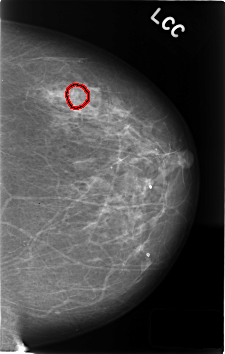

C_0408_1.LEFT_CC

FILE: C_0408_1.LEFT_CC.OVERLAY

TOTAL_ABNORMALITIES 1

ABNORMALITY 1

LESION_TYPE CALCIFICATION TYPE AMORPHOUS DISTRIBUTION CLUSTERED

ASSESSMENT 4

SUBTLETY 1

PATHOLOGY BENIGN

TOTAL_OUTLINES 1

BOUNDARY